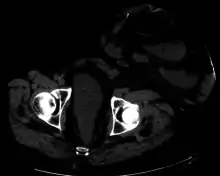

CT scan of same patient, showing intestines within the hernia.

Parastomal hernia is the most common late complication of stomata through the abdominal wall, occurring in 10 to 25% of the patients.[1]